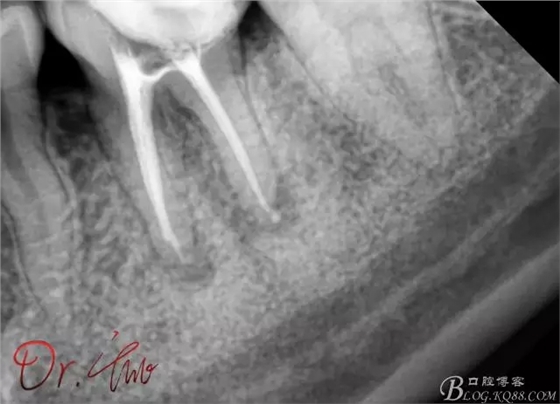

重點第二例病例,初診

拍片確定長度

試主尖,近中頰側(cè)形成臺階

試主尖,近中頰側(cè)再次拍片查看臺階位置及確定長度

試主尖,近中頰側(cè)試主尖,此時手用銼02錐度的已擴到30號,可以明顯感覺到臺階位置,挫預(yù)彎后找好正確位置可順利到達根尖,但是機用銼就是下不去,也是郁悶

試主尖,在30號02錐度K挫到達根尖后,用02錐度牙膠尖找準(zhǔn)位置,進行試尖

最后根充,明顯可看到臺階位置,期待預(yù)后效果